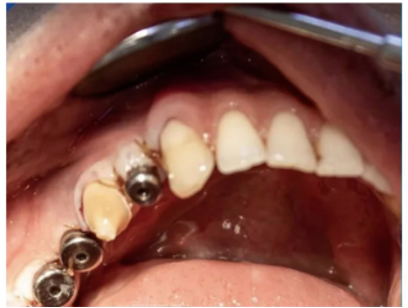

مرحله پنجم: در طول این دوران برای پر کردن فضای خالی و محافظت از ایمپلنت کاشته شده از healing استفاده می شود.

مرحله هفتم: روکش تیتانیومی یا زیرکویا روی اباتمنت متصل می شود.در اکثر مواقع چسب روکش ایمپلنت موقت است، به این دلیل که جراح شما بتواند هر زمان متوجه علامت و التهابی در اطراف ایمپلنت شد روکش را به راحتی خارج کند و اقدامات لازم برای رفع مشکل بوجود آمده را انجام دهد.